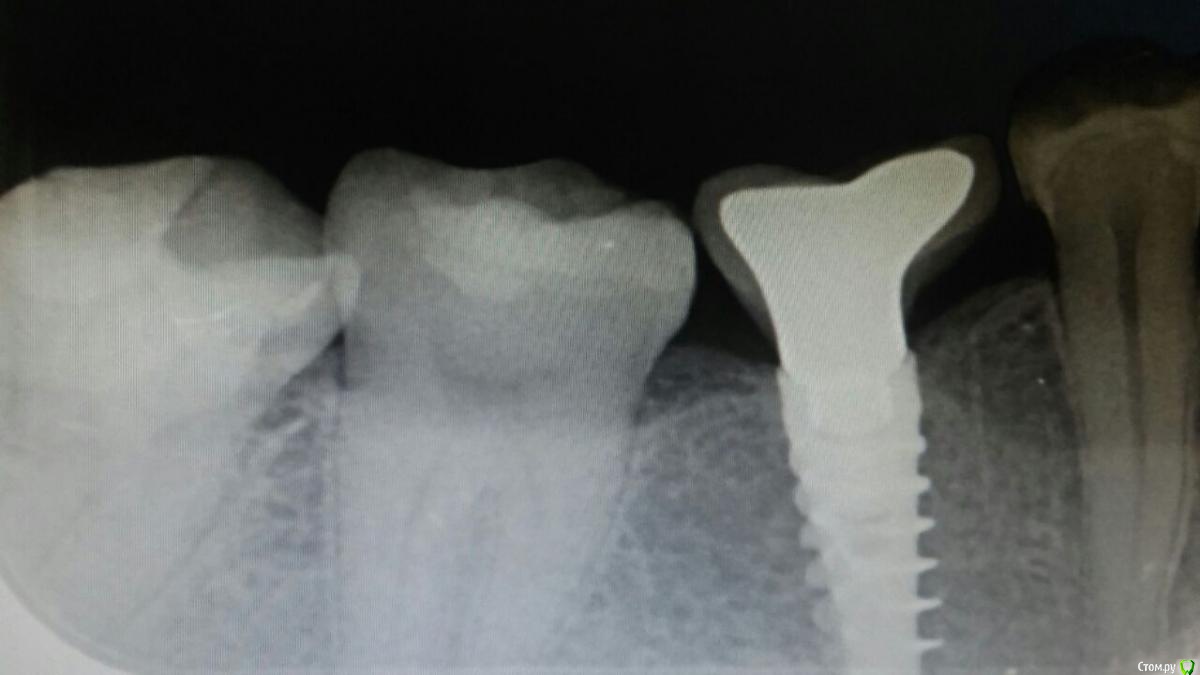

Liliya_imp Опубликовано 22 декабря, 2016 Поделиться Опубликовано 22 декабря, 2016 (изменено) Доброго времени суток, коллеги.Ситуация следующая: нужна замена коронки на импланте, исходная коронка с винтовой фиксацией.После раскрытия шахты и попытки открутить коронку стало понятно, что внутренние грани винта "стерлись", винт внутри абсолютно гладкий...Как можно открутить коронку? Возможно кто-либо сталкивался с подобной ситуацией.Имплант Альфа-био. Изменено 22 декабря, 2016 пользователем Liliya_imp Ссылка на комментарий

suballex Опубликовано 23 декабря, 2016 Поделиться Опубликовано 23 декабря, 2016 Доступ хороший,коронка на замену-разрезать все и абатмент тоже,будет доступ к винту.Поподробнее. Насколько понял я, из снимка - абатмет приливаемый. Как его разрезать, чтобы был доступ к винту? Ссылка на комментарий